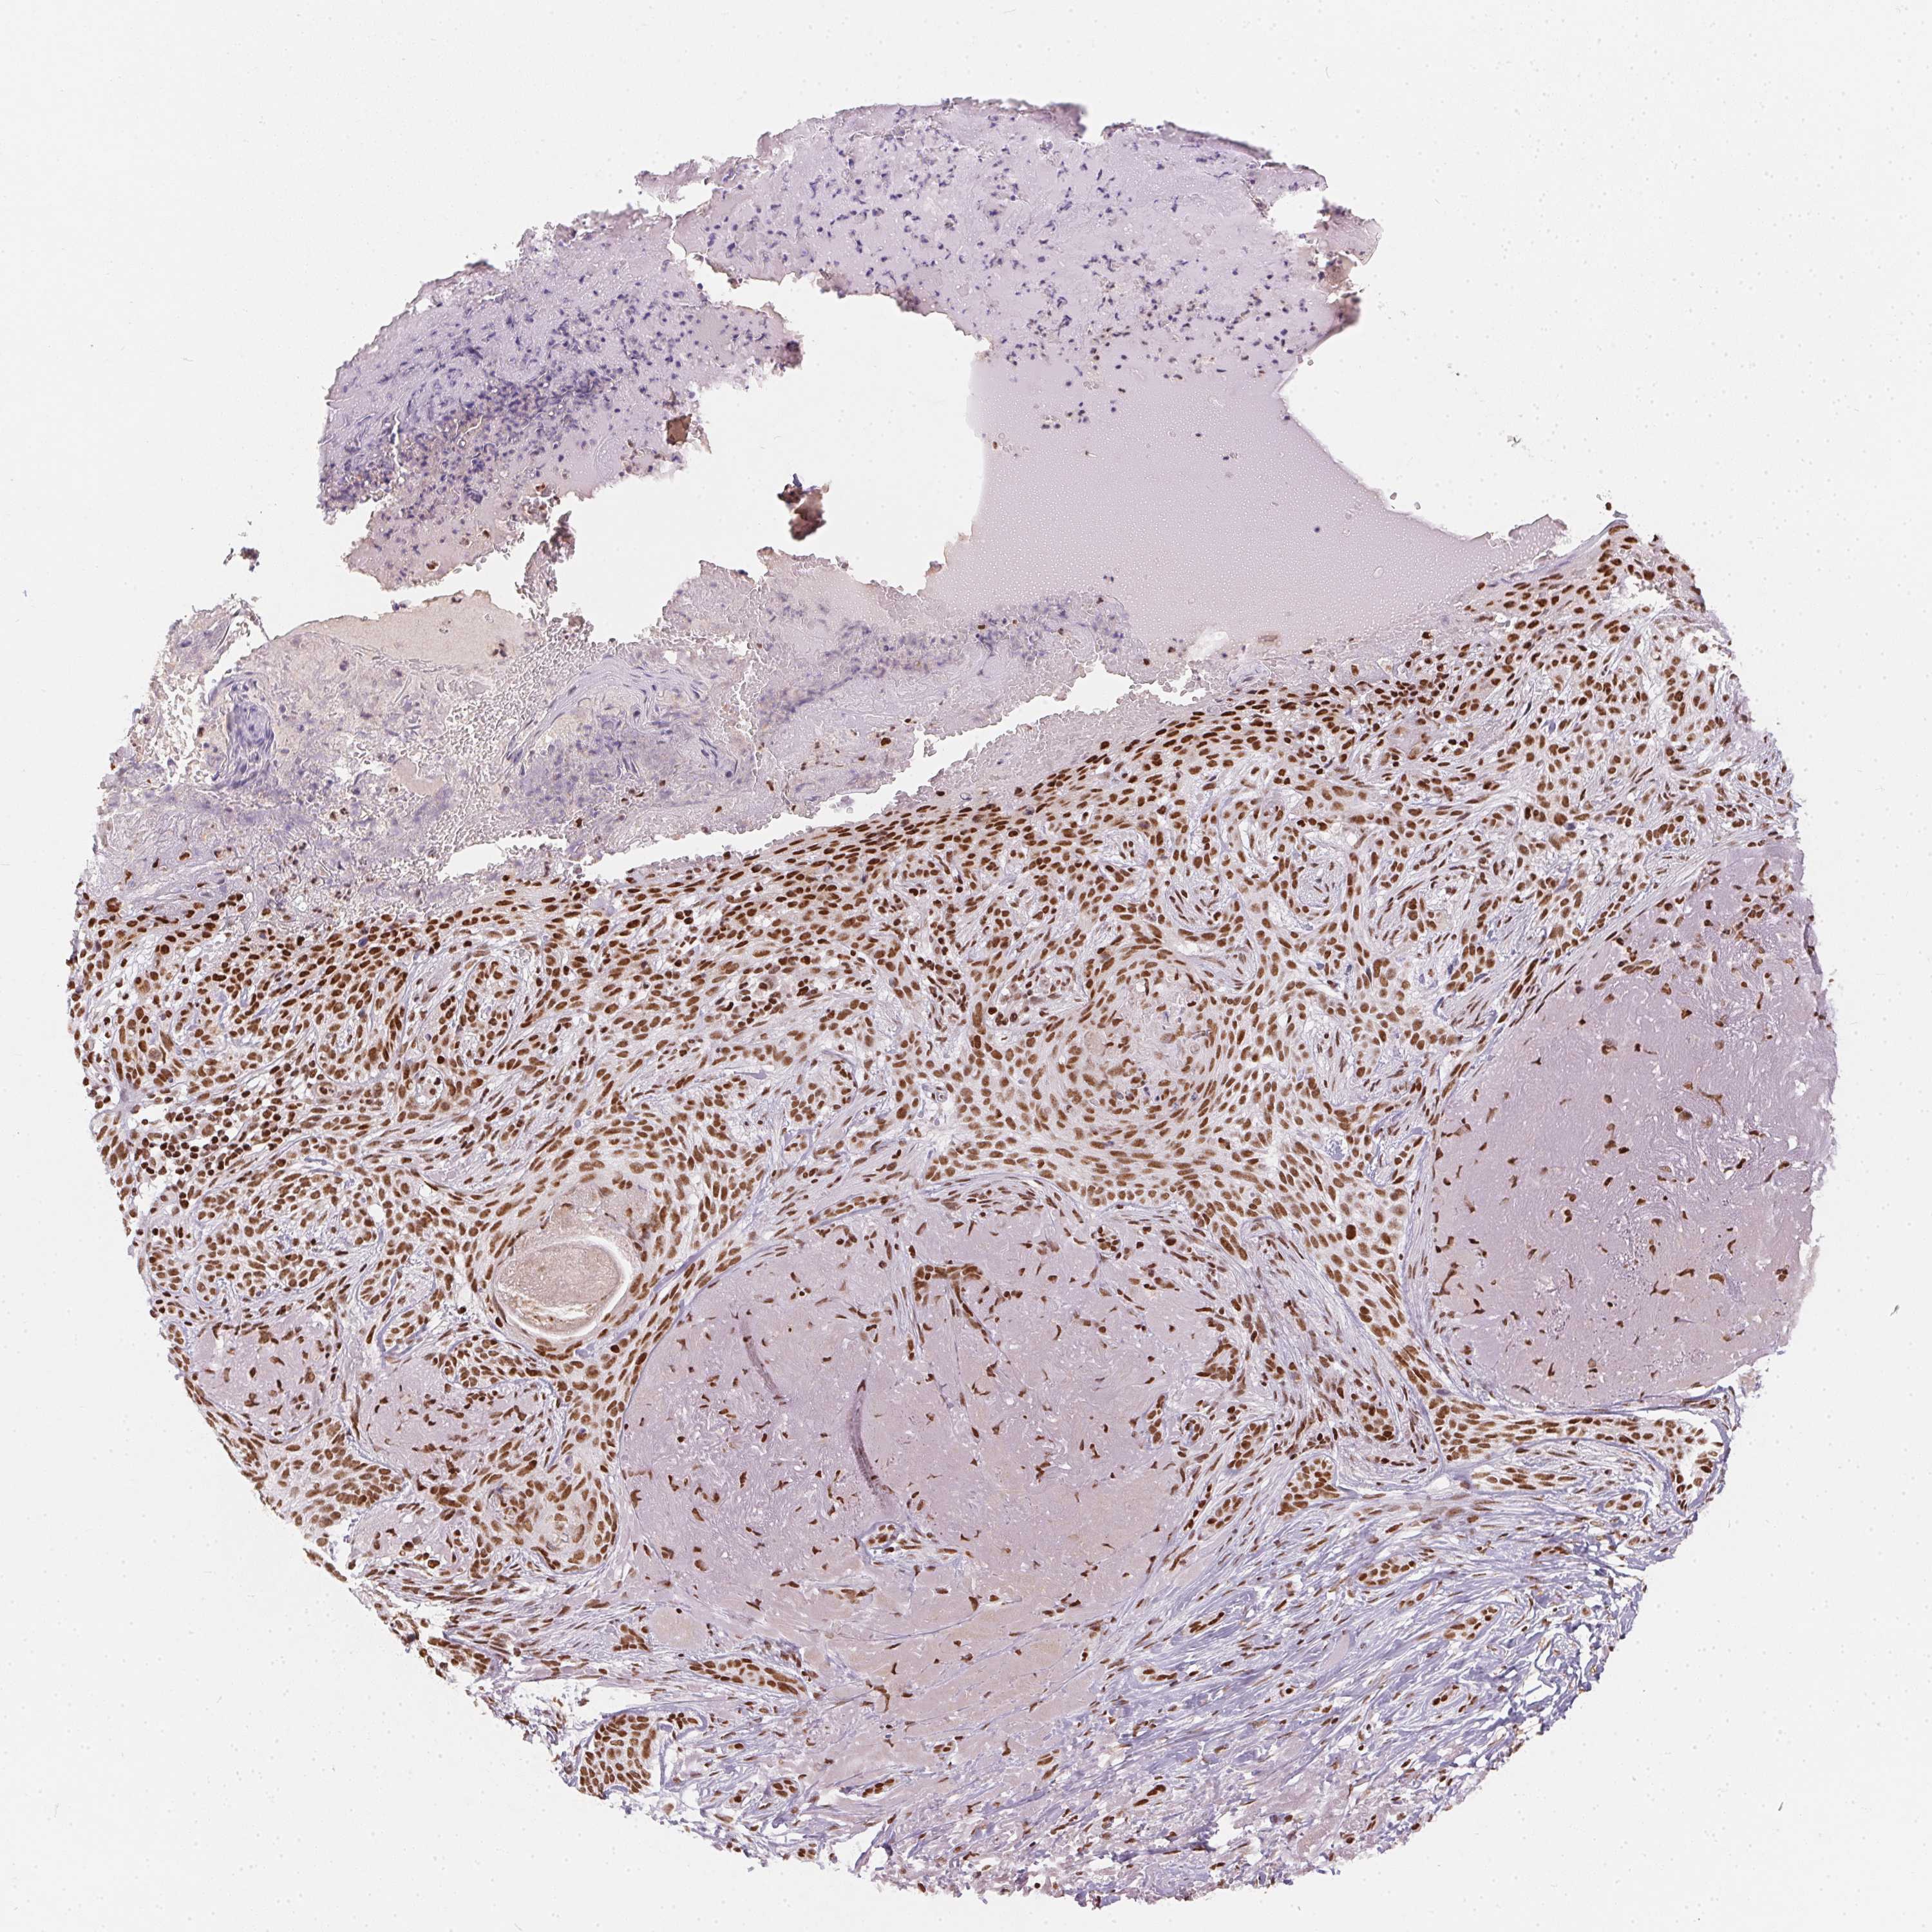

SKIN CANCER - Protein expressioni

A mouse-over function shows sample information and annotation data. Click on an image to view it in a full screen mode. Samples can be filtered based on level of antibody staining by selecting one or several of the following categories: high, medium, low and not detected. The assay and annotation is described here.

Each image is clickable and will lead to virtual microscopy that enables deeper exploration of all samples and also displays staining intensity scores, fraction scores and subcellular localization as well as patient and tissue information for each sample.

Antibody HPA064887

Staining

High

Medium

Low

Not detected

Intensity

Strong

Moderate

Weak

Negative

Quantity

>75%

75%-25%

<25%

None

Location

Nuclear

Cytoplasmic/membranous

Cytoplasmic/membranous,nuclear

Basal cell carcinoma